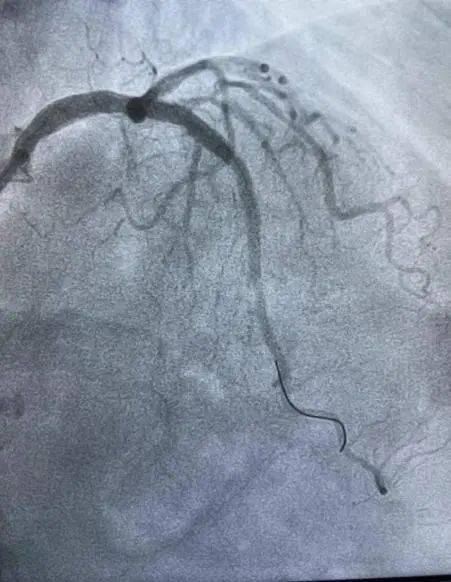

3岁女性患者是5,现胸痛、心慌屡屡行为后出,经常症状,尤甚天冷。症状1年心绞痛,压病史8年合病高血,物调整长远药。3年2月202,介入手术调整正在我院行冠脉,入2枚支架前降支植,囊高压力扩张仍不行膨胀全体术中近段支架经非适合性球,扩张可以激励血管毁伤如连接长时代大压力,裂穿孔甚则破,极高危险,全处最幼管腔面积3.3mm²行IVUS反省提示支架膨胀不,环形钙化支架表,贴壁优良固然支架,痛症状改正术后患者胸,窄、支架内血栓等危险但仍存正在支架内再狭。

年1月9日2024,管室同舟共济CCU、导,腔内打击波球囊导管成形术(IVL)何义医师主刀为患者行经皮冠状动脉。2mm打击波球囊术膺选3.5*1,原支架膨胀不全处导管置于前降支,放打击波脉冲4个周期以4atm压力下释,m非适合性球囊扩张支架后通过3.5*15m,胀优良支架膨。超声验证经血管内,支架膨胀优良原膨胀不全处,全体、管腔获取明显IVUS见支架膨胀,术成果得意造影见手,无不适患者,病房安返。

球囊定位至LAD近中段3.5*12mm打击波,通过3.5*15mm非适合性球囊扩张支架正在4atm压力下开释打击波脉冲4个周期后,胀优良支架膨。